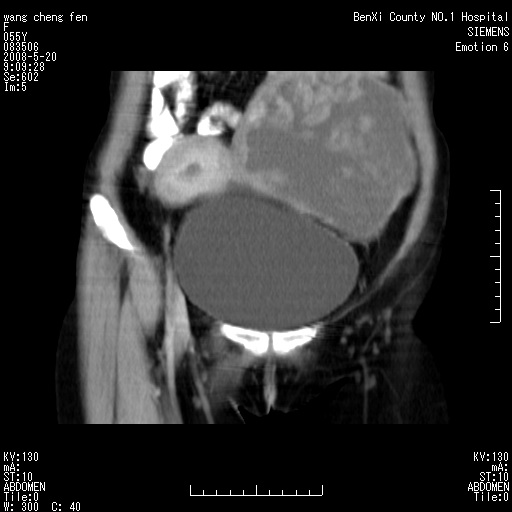

女、绝经后阴道流血3个月

左侧附件区巨大囊实性病灶,边缘光整,病灶囊壁较厚,增强示囊壁及实性部分明显强化,强化呈度与宫体实质大致相同,宫腔积液征像,未见盆腔积液等其他异常,考虑左侧卵巢囊腺癌,不除外囊腺瘤及浆膜下肌瘤坏死

左侧附件区巨大囊实性病灶,边缘光整,病灶囊壁较厚,增强示囊壁及实性部分明显强化,强化呈度与宫体实质大致相同,宫腔积液征像,未见盆腔积液等其他异常。绝经后阴道流血3个月,结合病史左侧卵巢囊腺癌首先考虑,宫腔扩大不除外累及。期待结果。

支持浆膜下子宫肌瘤.之前由于网络原因未看全图片,现在重看,宫颈见一类圆形低密度影,增强轻度强化,低于肌层强化,宫腔扩大,考虑宫颈癌伴宫腔积液可能性大.

囊实性肿块分隔厚度较大,厚薄不均,增强实性成分明显强化,有不规则阴道流血,卵巢囊腺癌可能性大。

1,宫颈部占位,宫颈癌?2,左侧附件区囊实性占位,界较清,实质部分强化明显。考虑浆膜下或阔韧带肌瘤囊变可能大。囊腺类肿瘤不除外。